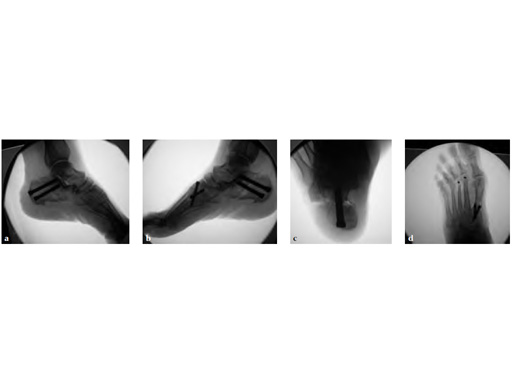

A medial displacement osteotomy of the calcaneus and transfer of the tendon of the flexor digitorum longus to the navicular fixed with an interference screw were performed (see Fig 2a-c). A fusion of the first medial cuneiformmetatarsal I, II, and III modified. Weil osteotomy was performed as well.

The talar axis is aligned to the midshaft of the first metatarsal (see Fig 3a-d).

A medializing calcaneal osteotomy was performed and fixed with two 6.5 mm HCS, a flexor hallucis longus transfer to her navicular is secured with an interference 7 mm screw and a lapidus procedure fixed with two crossing 4.5 HCS (see Fig 2a-b).

Progressive weight bearing was permitted at 8 weeks and UCBL was advised until the fourth postoperative month (see Fig 3a-b).